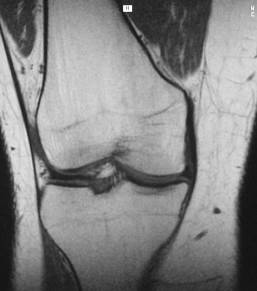

Collateral ligaments

normal

T1 sag

Thickened

ligament, not

purely black